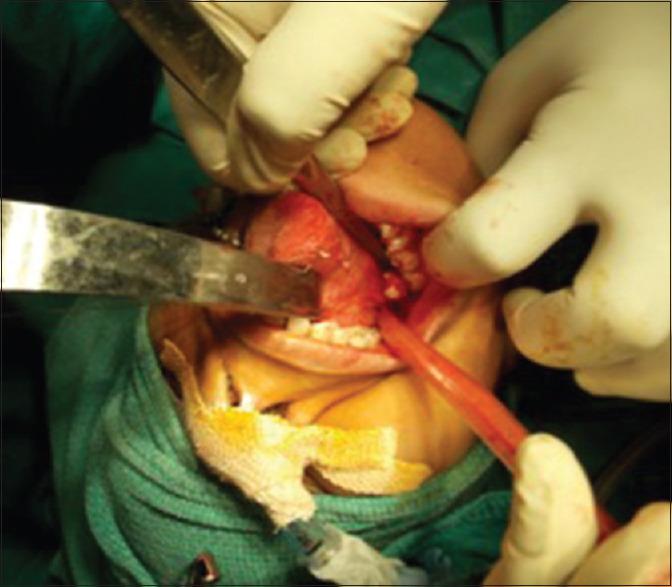

Iatrogenic displacement of a tooth or tooth fragment is a rare but well-recognized complication that occurs during exodontia. The most common sites of dislodgment of a mandibular third molar fragment are the sublingual, submandibular, and pterygomandibular and lateral pharyngeal spaces. Removal of a displaced tooth from these spaces may be complex due to poor visualization and limited access. A thorough evaluation of all significant risk factors along with precise localization of the tooth by clinical and radiographic means should be performed to prevent untoward complications. This paper reports two cases of iatrogenic displacement of mandibular third molar teeth, in the sublingual space and lingual pouch. Both the cases were managed intraorally under general anesthesia, and the postoperative healing was satisfactory and uncomplicated. A brief review of literature is also provided in this paper.

摘要

牙齿或牙碎片的医源性移位是拔牙过程中一种罕见但已被充分认识的并发症。下颌第三磨牙碎片最常见的移位部位是舌下、颌下、翼下颌和咽旁间隙。由于视野不佳和操作空间有限,从这些间隙取出移位的牙齿可能很复杂。应通过临床和影像学手段对所有重要危险因素进行全面评估,并精确确定牙齿位置,以预防不良并发症。本文报告了两例下颌第三磨牙医源性移位至舌下间隙和舌袋的病例。两例均在全身麻醉下经口处理,术后愈合良好,未出现并发症。本文还对相关文献进行了简要综述。